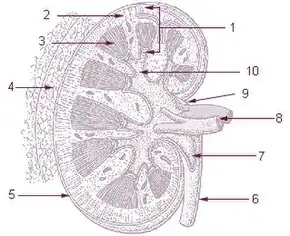

Kidney -

Renal cortex

Renal cortex